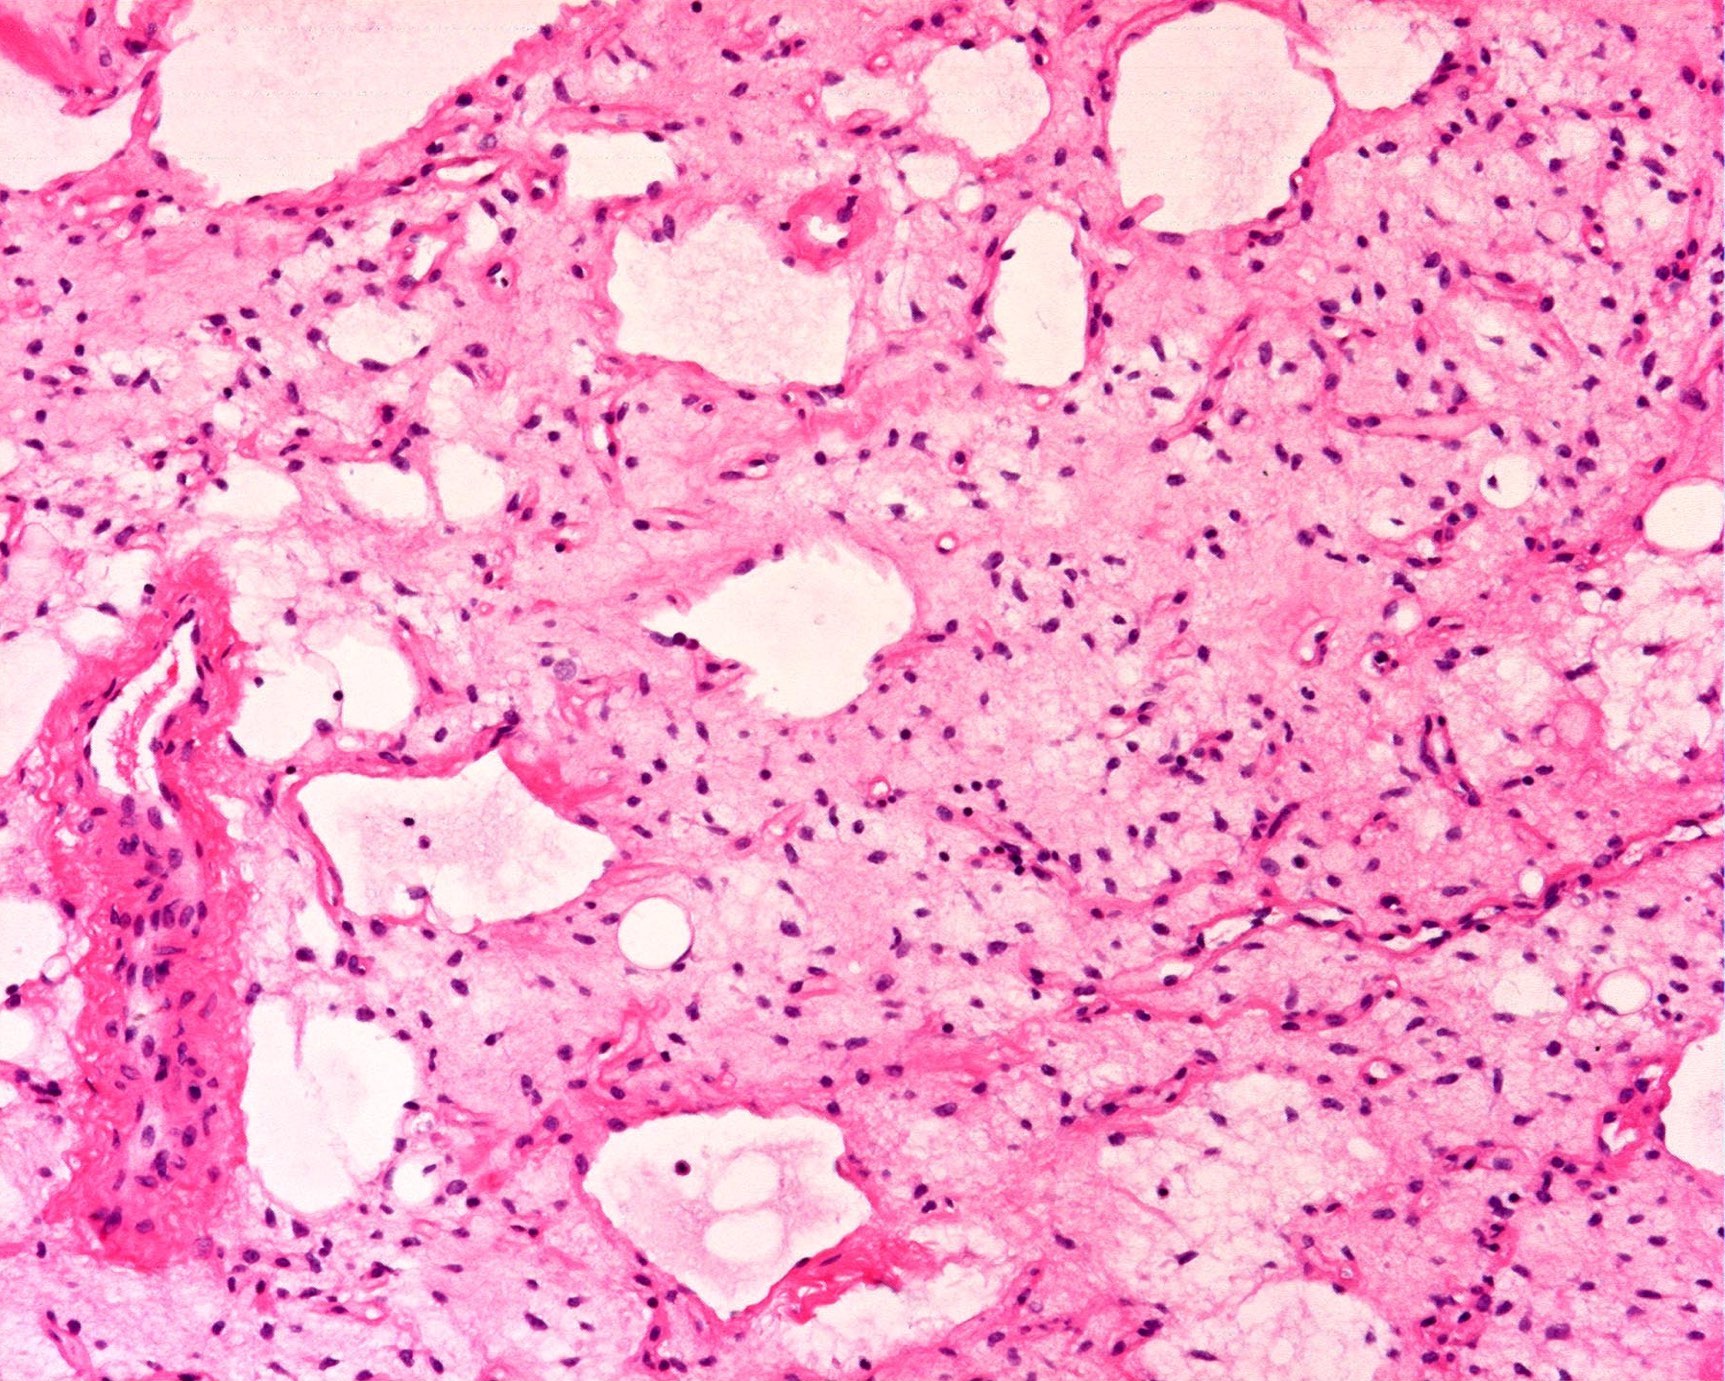

Microscopic (histologic) description

- Low grade

- Paucicellular with monomorphic, stellate or fusiform shaped cells without atypia; striking in their blandness, so much so that any significant pleomorphism should cause one to pause

- Prominent plexiform vasculature (delicate thin walled arborizing and curving capillaries that form a network reminiscent of chicken wire fencing)

- These are striking because of the overall background paucicellularity and are still present in high grade tumors but are much less obvious

- Numerous signet ring lipoblasts, particularly at periphery of lobules

- This imparts a lipoblastoma-like appearance (see Differential diagnosis)

- Mucoid matrix is rich in hyaluronic acid that may form large mucoid pools (so called pulmonary edema pattern)

- Will be positive for stromal mucin stains such as Alcian blue (see Microscopic (histologic) images)

- Typically there is no significant mitotic activity

The microscopic image above depicts the histologic appearance of a soft tissue mass resected from the thigh of a 37 year old man and is representative of the entire lesion. Which of the following is true regarding the diagnosis?

D. Majority of cases harbor t(12;16) FUS::DDIT3 gene fusion. The microscopic image depicts a low grade myxoid liposarcoma characterized by a proliferation of bland stellate tumor cells embedded in a myxoid matrix with a prominent plexiform capillary network and scattered signet ring lipoblasts. There is no mitotic activity or pleomorphism. The majority of cases of myxoid liposarcoma harbor a t(12;16) FUS::DDIT3 gene fusion. Answers B and C are incorrect because the t(9;22) EWSR1::NR4A3 gene fusion is characteristic of extraskeletal myxoid chondrosarcoma and the t(7;16) FUS::CREB3L2 gene fusion is characteristic of low grade fibromyxoid sarcoma. Answer E is incorrect because classification of myxoid liposarcoma as high grade requires > 5% of the sampled lesion to consist of a hypercellular round cell component according to the WHO. Cases with borderline round cell component (< 5%) are regarded as having areas of transition, a designation of unclear diagnostic significance. Answer A is incorrect because immunohistochemistry for MDM2 is negative in myxoid liposarcomas.